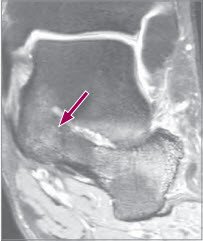

In Einzelfällen ist diese Verbindung nicht klar sichtbar, vor allem, wenn diese noch rein fibrös oder fibrokartilaginär vorliegt. In diesen Fällen empfiehlt sich eine MRI-Untersuchung (Abb. 3). In Einzelfällen führen wir zur Diagnosesicherung eine Infiltration im calcaneonavicularen Übergangsbereich durch. Zeigt sich eine unmittelbare Schmerzlinderung, ist die Diagnose gesichert.